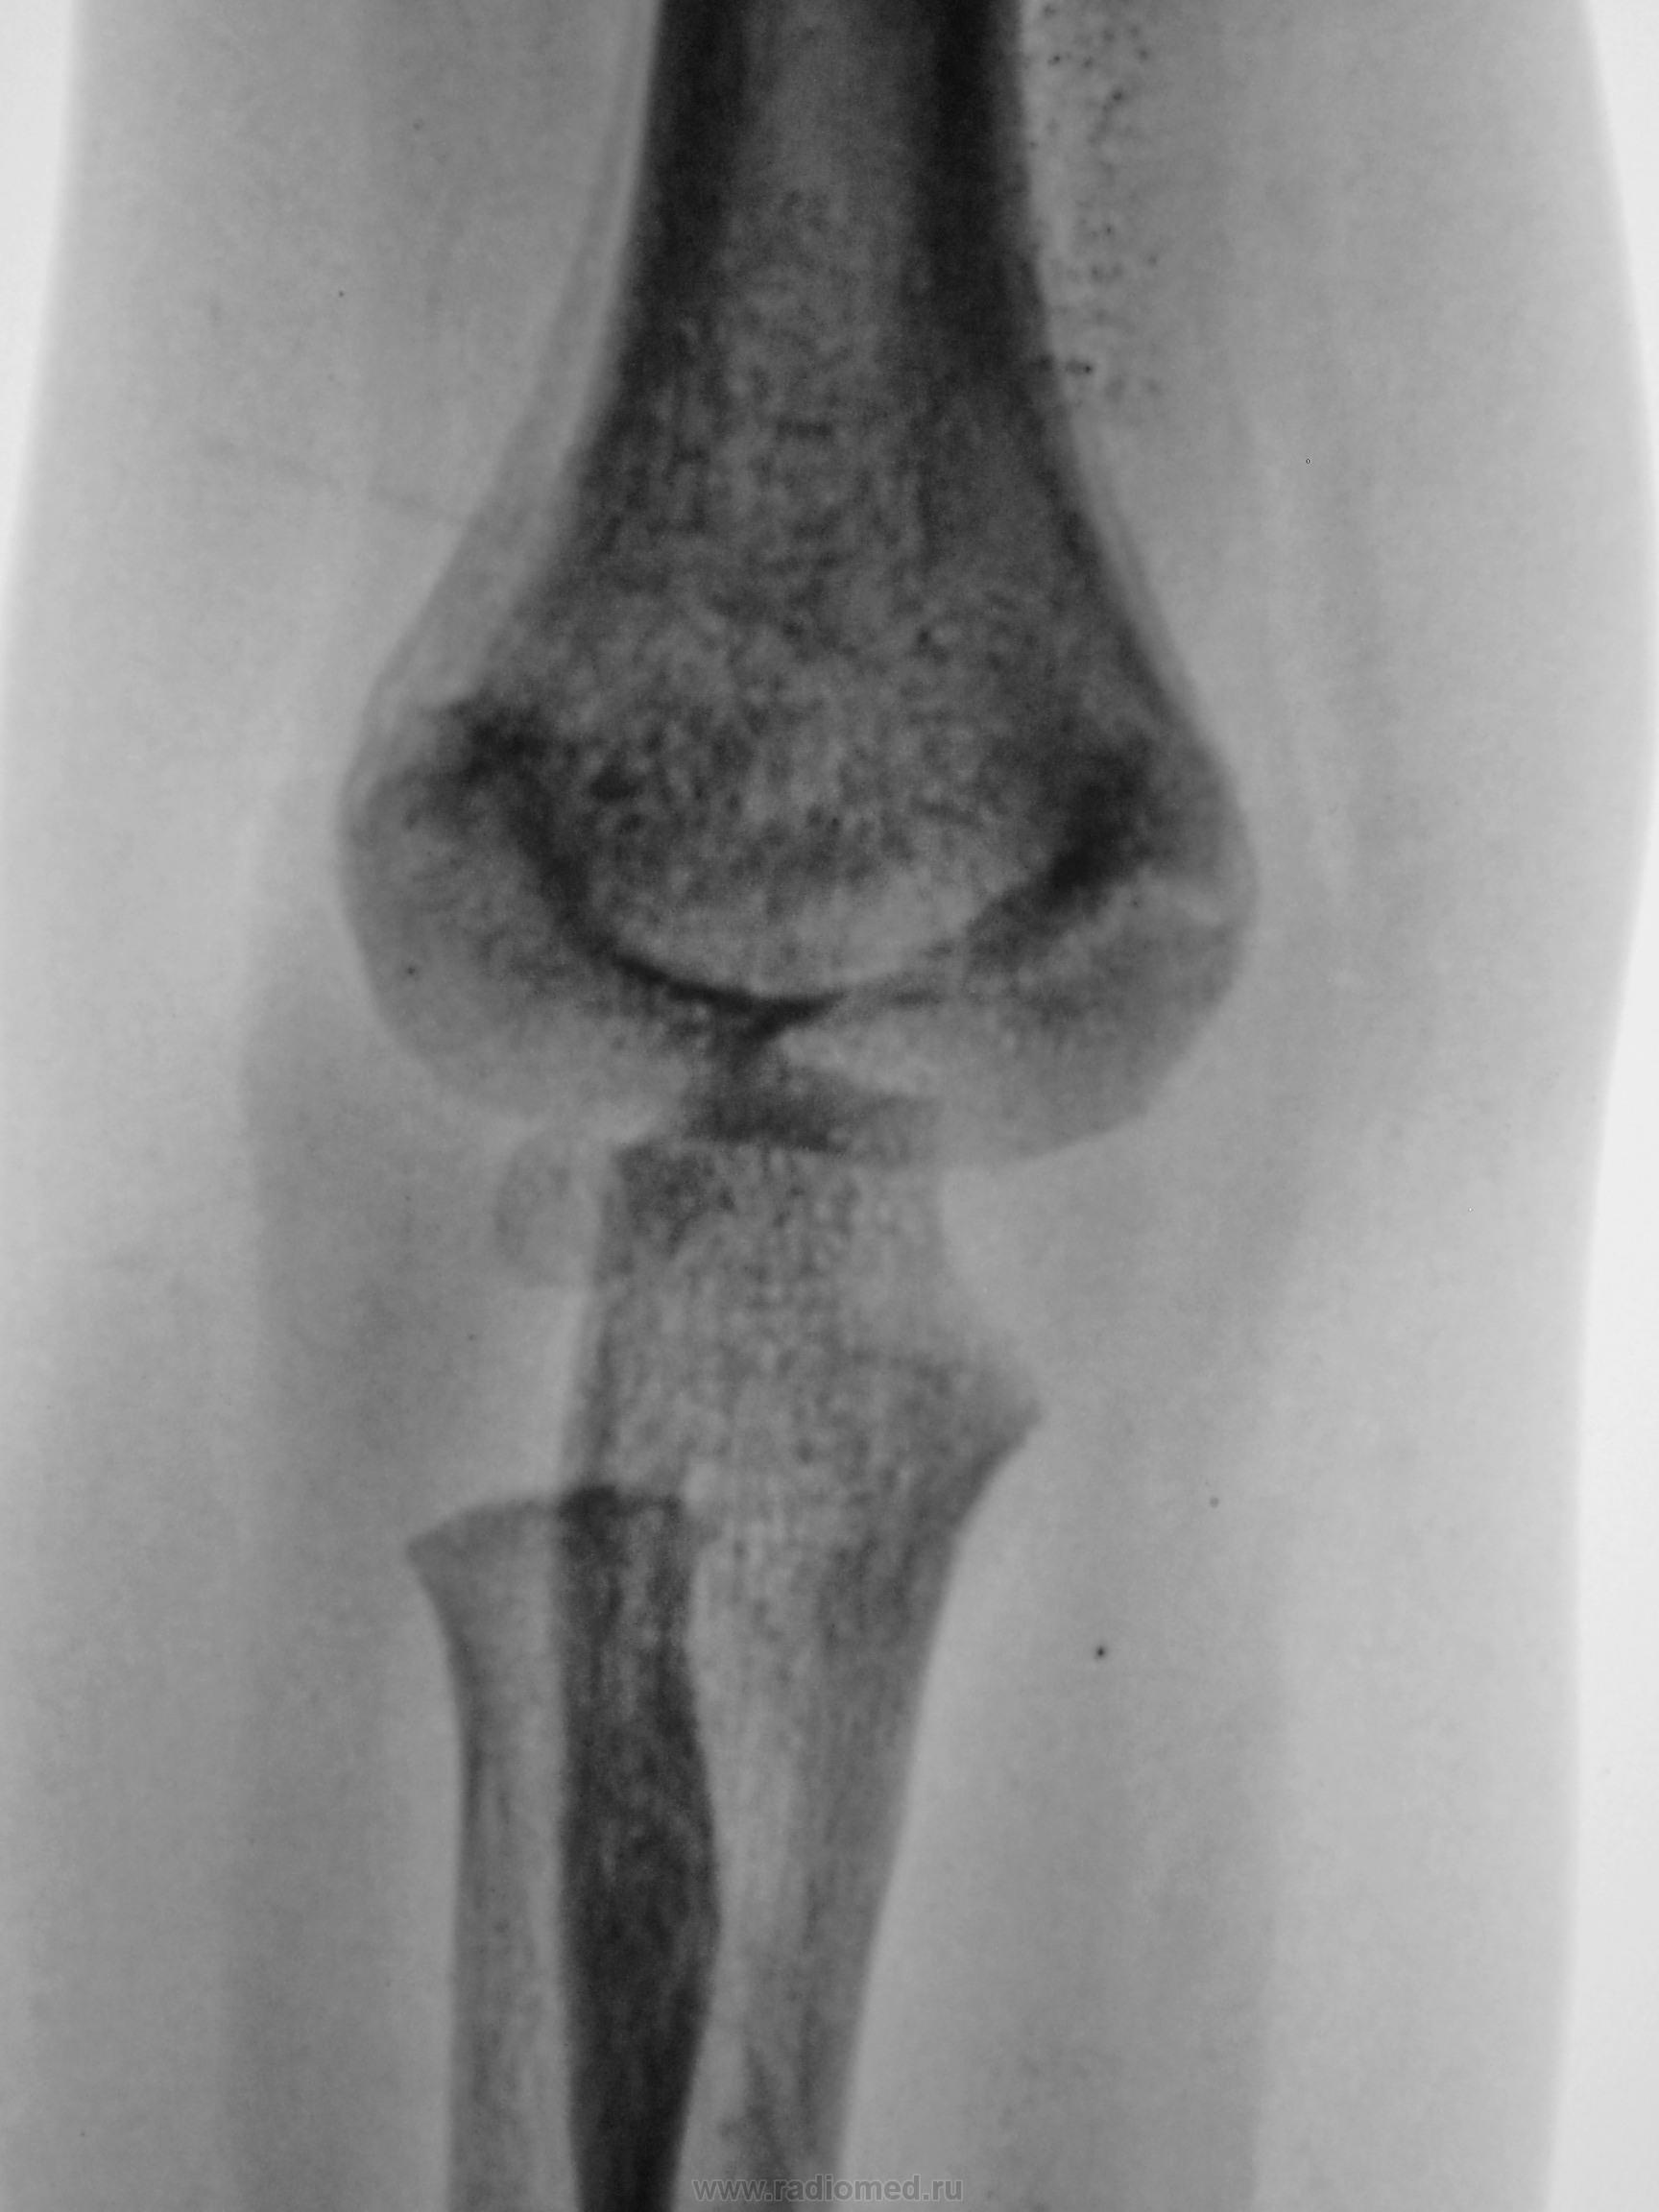

Ребенок. Снят гипс.

3 года.

Консолидирующийся чрезмыщелковый перелом плечевой кости. Есть, конечно, угловое смещение кзади, надо было сразу репонировать, а теперь не знаю, может, для такого возраста можно и оставить.

чрезмыщелковый перелом плечевой кости,c подвывыхom головки лучевой  кости

чрезмыщелковый перелом плечевой кости,c подвывыхom головки лучевой  кости с смешением вниз……

Обычный срастающийся с допустимым смещением чрезмыщелковый перелом. Подвывихов нет.

Мне кажется что сдесь может быть остеолитический процесс( остеоS-ma) плечевой кости.